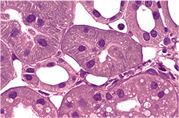

• paraffin embedding and sectioning of tissues

• histological stainings: HE, alcian blue, reticulin, ...